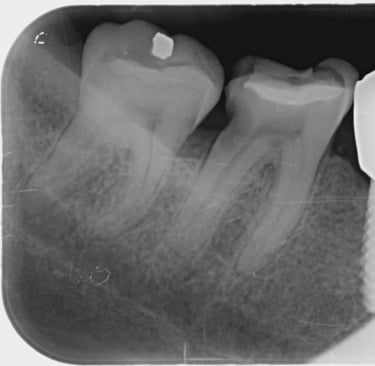

Con motivo de una revisión dental, se toman radiografías interproximales (de aleta de mordida) según sea necesario. Se toman 1 o 2 de cada lado de la boca. Si tiene caries muy activas , puede que sean necesarias radiografías interproximales con mayor frecuencia. Estas radiografías se toman para detectar caries en los espacios interdentales y para comprobar el nivel óseo.

En las radiografías interproximales se puede observar el inicio de las caries antes de que sean visibles en la boca. Por lo tanto, es posible iniciar un tratamiento preventivo antes de realizar un empaste. Las radiografías interproximales también permiten evaluar el nivel óseo alrededor de los dientes y, por consiguiente, indicar si existe periodontitis.